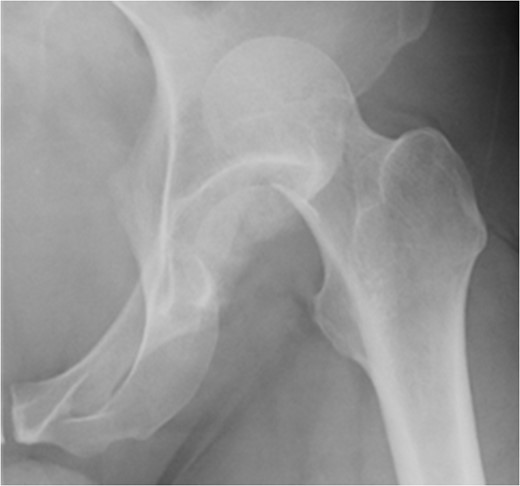

At 14 months postoperative, the patient is pleased with his progress. There is no radiographic evidence of avascular necrosis at this stage (Figs 6 and 7). He regularly participates in activities such as cycling, and scores well on the modified Harris Hip Score (81/100), non-arthritic hip score (92.5/100) and SF-12 (41/48).